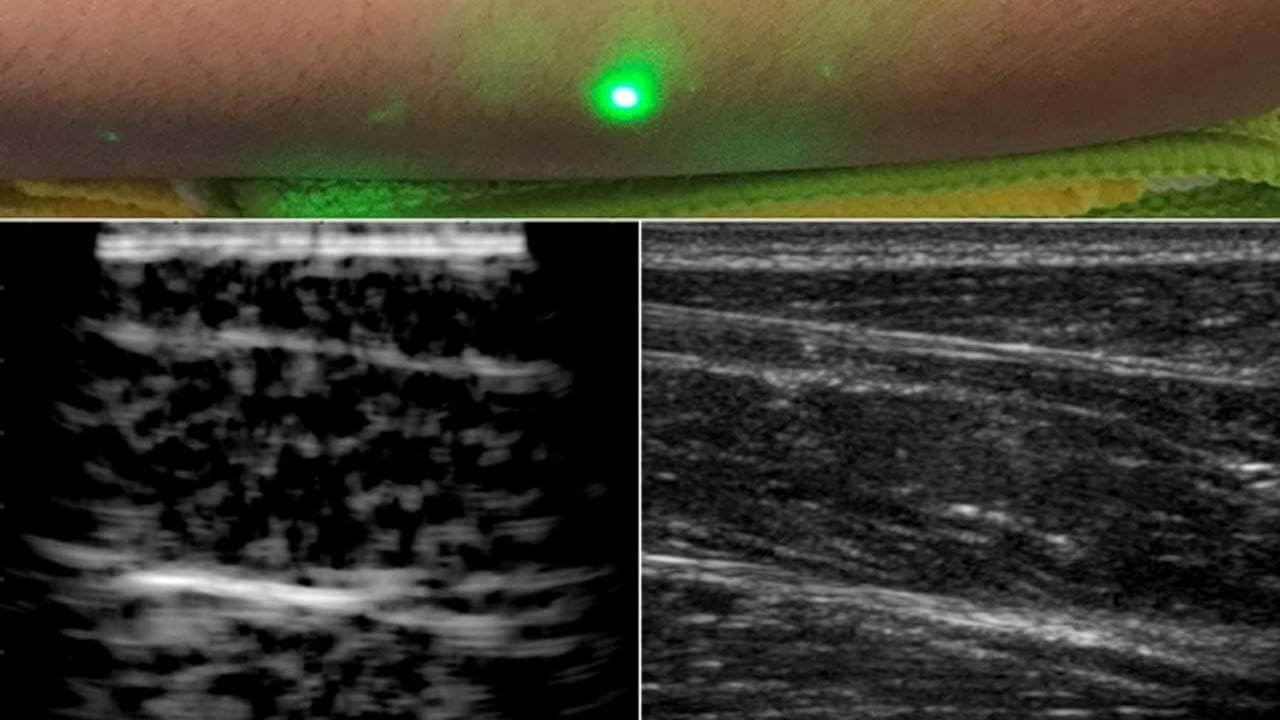

Вот такой луч способен сделать УЗИ не хуже контактного прибора

Если присмотреться, можно увидеть кость

Испытания проходили с помощью четырех добровольцев, на предплечья которых проецировались лазерные лучи. По итогу исследования ученые получили снимки предплечья, на которых видно не только кожу и мышцы, но и кость. Далее результаты сравнили с данными, полученными с помощью классического способа УЗИ, чтобы убедиться в правдивости показаний.